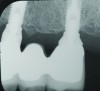

Fig 7 through Fig 14. Periapical radiographs of a 62-year-old woman who received a fixed porcelain-fused-to-metal reconstruction supported by abutments by internally connected dental implants. Fig 7 through Fig 10 are at initial prosthesis placement: mandibular site Nos. 30 and 29 (Fig 7); mandibular site Nos. 26, 25, and 23 (Fig 8); mandibular site Nos. 23 and 21 (Fig 9); mandibular site Nos. 21 through 19 (Fig 10). Fig 11 through Fig 14 are 11 years later (2013) and show excellent preservation of the vertical bone levels around the implants: mandibular site Nos. 30 and 29 (Fig 11); mandibular site Nos. 26 and 25 (Fig 12); mandibular site Nos. 25 and 23 (Fig 13); mandibular site Nos. 20 and 19 (Fig 14). It is interesting to note that in the mandibular right posterior quadrant there is a matched pair, ie, an external hex dental implant (No. 30) adjacent to an internally connected dental implant (No. 29). The bone levels around each of these designs are well-preserved at the 11-year follow-up.

Figure 8